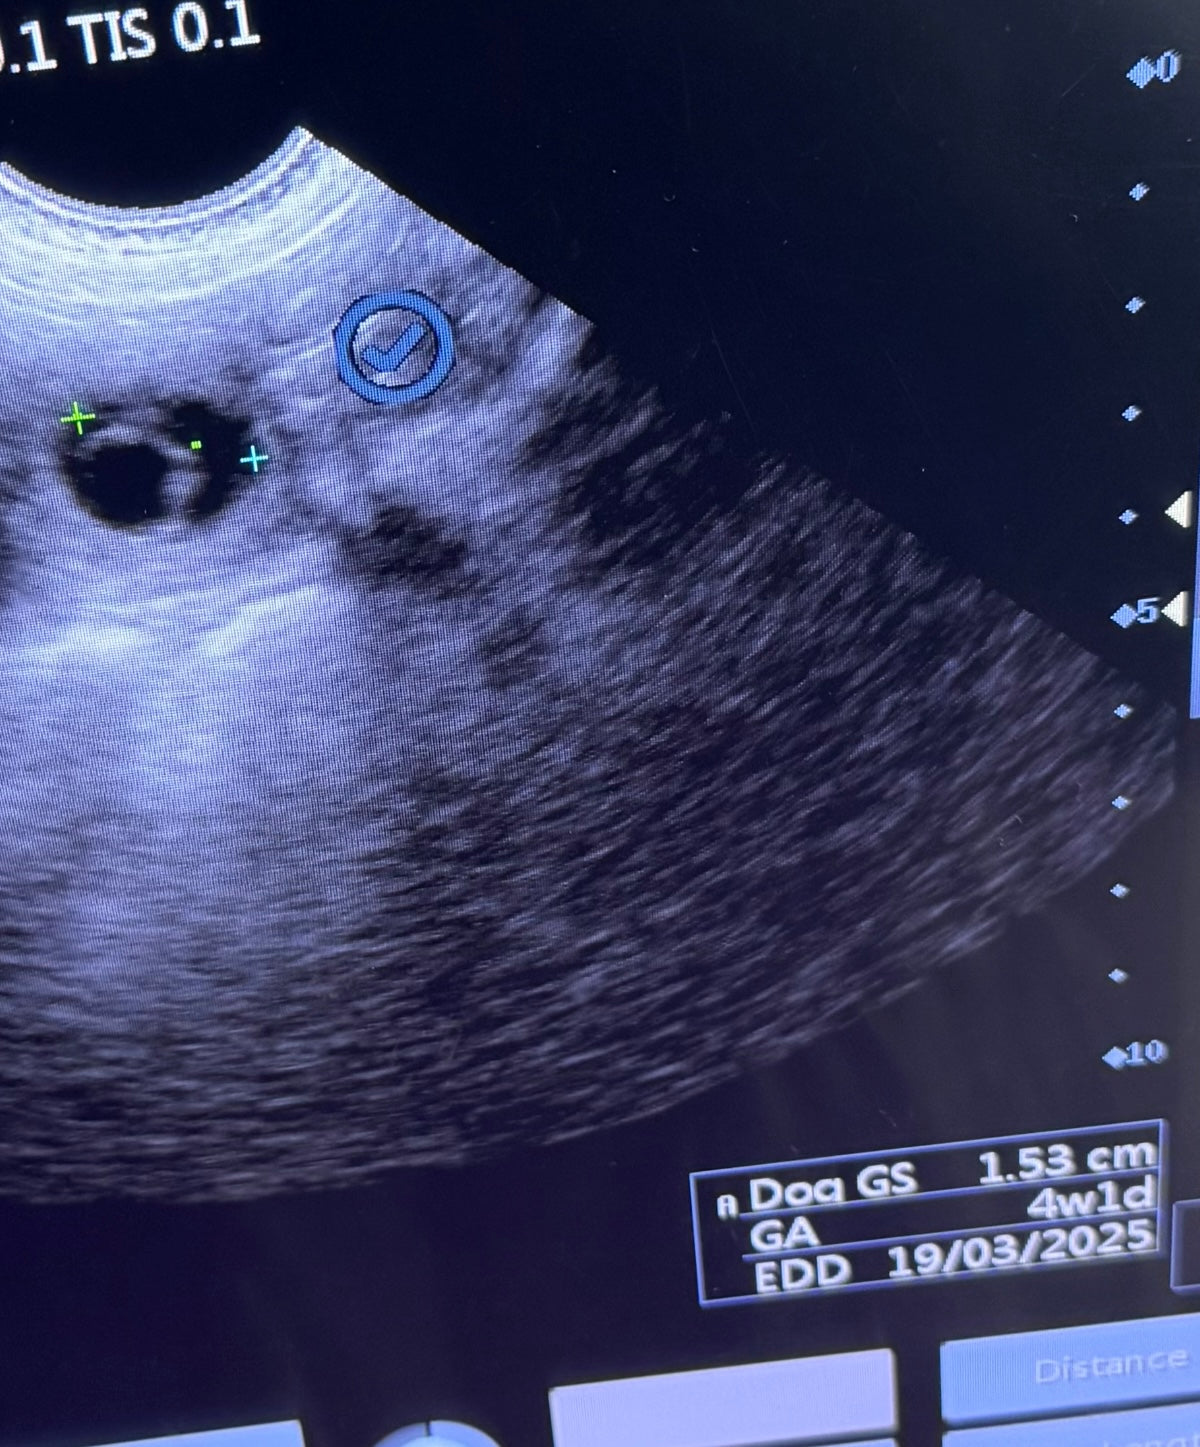

Gestational Sac (GS):

This is the measurement of the full gestational sac and is most accurate during the early stages of pregnancy (26-35 days)